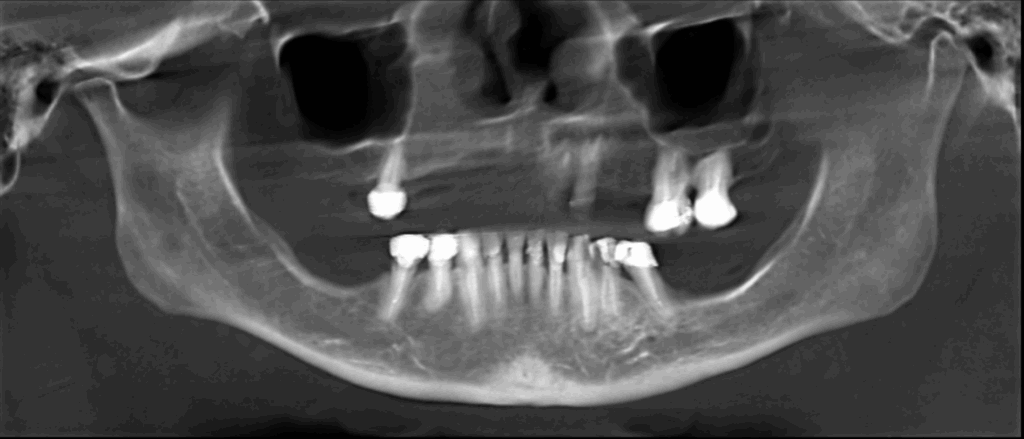

En la reformación panorámica (Figura 1), se aprecia aplanamiento de los contornos de los cóndilos mandibulares, además se observa imagen radiolúcida unilocular proyectada sobre cóndilo mandibular izquierdo, de limites definido, bordes corticalizados.

Radiografia Panorámica

A la evaluación de la tomografía volumétrica (CBCT) de la ATM en boca cerrada, en los cortes axiales (Figura 2), coronales (Figura 3) y sagitales (Figura 4), se aprecia aplanamiento de la vertiente posterior del cóndilo mandibular del lado izquierdo con presencia de imagen hipodensa localizado próximo a la vertiente superior compatible con quiste subcondral, además se aprecia disminución de espacio articular posterior en ATM izquierda y disminución del espacio articular anterior en ATM derecha.